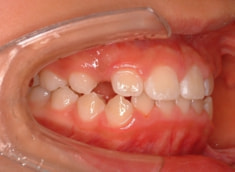

治療開始から約10ヶ月後